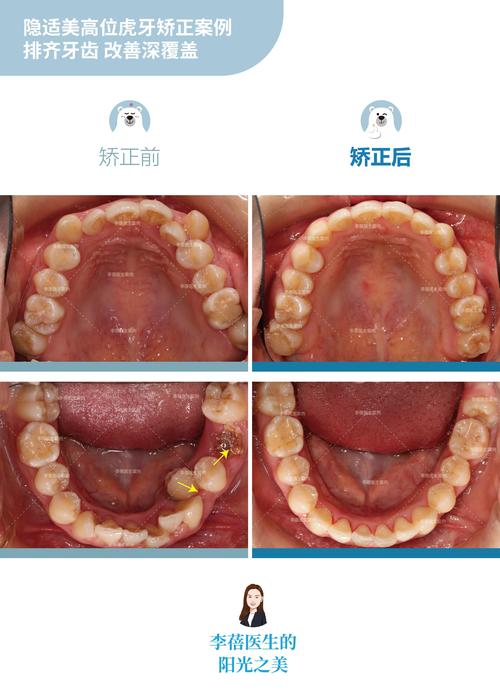

| 隐形矫正(国产品牌) | 15000-35000 | 可自行摘戴,美观舒适,方便清洁,适合轻度至中度错颌畸形 | 职场人士、学生,注重美观和便利 |